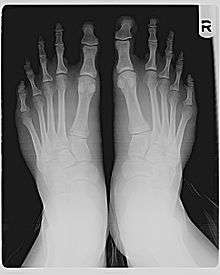

The metatarsal bones behind the toes vary in relative length. For most feet, a smooth curve can be traced through the joints at the bases of the toes. But in Morton's foot, the line has to bend more sharply to go through the base of the big toe, as shown in the diagram.

This is because the first metatarsal, behind the big toe, is short compared to the second metatarsal, next to it. The longer second metatarsal puts the joint at the base of the second toe (the second metatarsal-phalangeal, or MTP, joint) farther forward.

If the big toe and the second toe are the same length (as measured from the MPT joint to the tip, including only the phalanges), then the second toe will protrude farther than the big toe, as shown in the photo. If the second toe is shorter than the big toe, the big toe may still protrude the farthest, or there may be little difference, as shown in the X-ray.